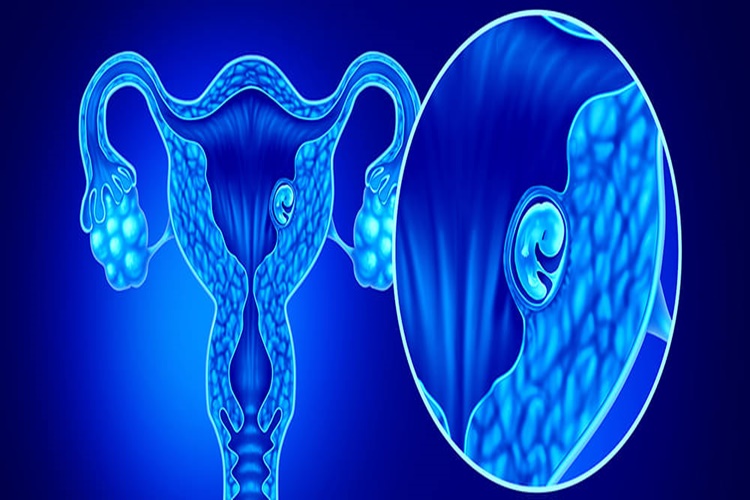

Evet, yumurtalık kanserinin tedavisi mümkün olabilir. Ancak,

tedavi planı hastanın kanserin tipine, evresine, yaşına ve genel sağlık

durumuna bağlı olarak değişebilir. Yumurtalık kanseri tedavisinde genellikle

bir veya daha fazla aşama kullanılır ve bu aşamalar şunları içerebilir:

Cerrahi Müdahale: Yumurtalık kanserinin tedavisinde cerrahi

müdahale sıklıkla kullanılır. Cerrahi, yumurtalıkların ve belirli durumlarda

çevreleyen dokuların çıkarılmasını içerebilir. Bu prosedür, kanserin ne kadar

yayıldığına bağlı olarak farklı seviyelerde gerçekleştirilebilir.

Kemoterapi: Cerrahi sonrası veya bazı durumlarda cerrahi

öncesinde kemoterapi (ilaç tedavisi) kullanılabilir. Kemoterapi, kanser

hücrelerini öldürmeyi veya büyümelerini yavaşlatmayı hedefler. Yumurtalık

kanserine karşı kullanılan kemoterapi ilaçları özellikle etkilidir.

Radyoterapi: Radyoterapi, kanser hücrelerini yok etmek veya

kontrol altına almak için yüksek enerjili ışınları kullanır. Ancak, yumurtalık

kanseri tedavisinde radyoterapi nadiren kullanılır ve genellikle diğer tedavi

yöntemlerine tercih edilmez.

Hormon Tedavisi: Hormon tedavisi, yumurtalık kanseri

hücrelerinin büyümesini kontrol etmek amacıyla kullanılabilir. Bu tedavi

özellikle bazı yumurtalık kanseri türlerine karşı etkilidir.

Hedefe Yönelik Tedavi: Bazı yumurtalık kanseri vakalarında,

kanser hücrelerinin belirli hedeflere yönelik tedavi ile hedeflenmesi mümkün

olabilir. Bu tedavi genellikle daha ileri evrelerde kullanılır.

Yumurtalık kanserinin erken teşhisi, tedavi şansını

artırabilir. Bu nedenle, yumurtalık kanseri belirtileri (karın şişliği, karın

ağrısı, hazımsızlık, iştah kaybı, sık idrara çıkma vb.) gözlemlendiğinde veya

risk faktörleri mevcut olduğunda bir sağlık profesyoneline başvurmak önemlidir.

Tedavi planı, hastanın özgün durumuna göre özelleştirilir ve

bir onkolog (kanser uzmanı) tarafından yönlendirilir. Yumurtalık kanseri

tedavisi, genellikle cerrahi, kemoterapi veya bu tedavi yöntemlerinin bir

kombinasyonu içerebilir. Her hasta için en uygun tedavi seçenekleri ve

sonuçları, hastanın spesifik durumuna bağlı olarak değerlendirilmelidir.